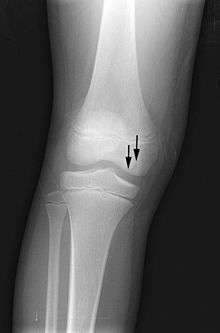

X-ray images of avascular necrosis in the early stages usually appear normal. In later stages it appears relatively more radio-opaque due to the nearby living bone becoming resorbed secondary to reactive hyperaemia.[1] The necrotic bone itself does not show increased radiographic opacity, as dead bone cannot undergo bone resorption which is carried out by living osteoclasts.[1] Late radiographic signs also include a radiolucency area following the collapse of subchondral bone (crescent sign) and ringed regions of radiodensity resulting from saponification and calcification of marrow fat following medullary infarcts.

Radiography of total avascular necrosis of right humeral head. Woman of 81 years old with diabetes of long evolution.

Radiography of avascular necrosis of left femoral head. Man of 45 years old with AIDS.